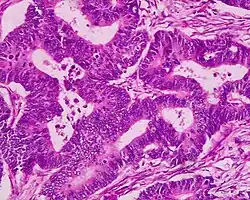

étude au microscope d'un adénocarcinome révélant des vacuoles contenant de la mucine. Coloration de Papanicolaou..

Adénocarcinome, hautement différencié, au niveau du rectum.

Un adénocarcinome est une tumeur maligne développée aux dépens d'un épithélium glandulaire. Le terme est à distinguer de celui d'adénome qui désigne une tumeur développée aux dépens d'un épithélium glandulaire, mais bénigne. En pratique, une tumeur est reconnue comme adénocarcinome lorsque son analyse microscopique anatomo-pathologique démontre un aspect de glande (tubes glandulaires) ou la présence de sécrétions mucineuses (muco-sécrétions).